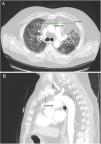

Imaging analysisA pre-transplant chest CT-scan with intravenous contrast was performed in all patients, as part of the routine assessment of LT candidates. Scans were obtained at 10mm intervals in the supine position at end inspiration. The CT scan Digital Imaging Communications in Medicine (DICOM) format was used for assessment of axes and AMF volume.

A standardized manual tracing on the chest CT-scan was performed by two independent readers, blinded to each other. The radiological measurements of AMF included:

Anteroposterior axis (AP): from the posterior wall of sternum to the anterior wall of pulmonary artery, measured in the CT-axial plane (Fig. 2).

Transverse axis (T): distance between both mediastinal pleurae, obtained at the same level of AP axis, and measured in the CT-axial plane (Fig. 2).

Height (H): from posterior wall of the sternal notch to the main pulmonary artery trunk, measured in the sagittal plane (Fig. 2).

AMF volumes (V) were calculated by using the formula: AP×T×H×3.14/6, following a similar method to calculate prostatic volumes.10